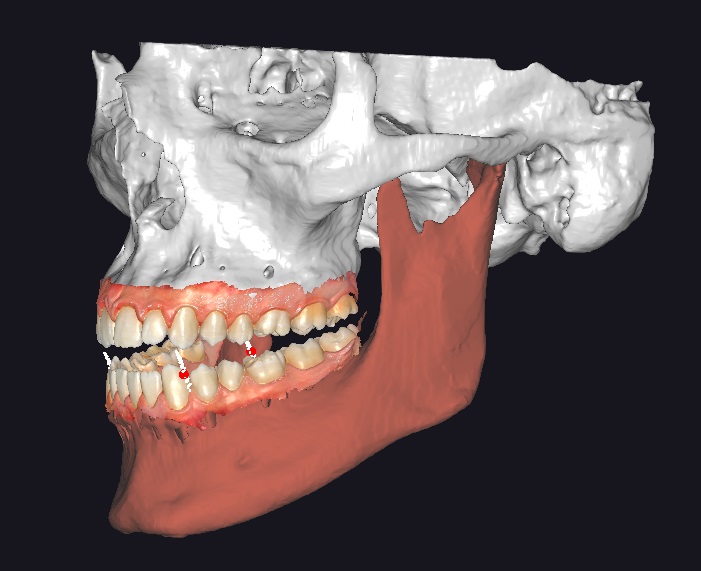

Nel nostro studio, ci avvaliamo della TAC odontoiatrica Cone Beam, una tecnologia diagnostica avanzata che permette di ottenere immagini tridimensionali dettagliate delle arcate dentarie e delle strutture ossee circostanti. Questo esame offre una visione completa del cavo orale, migliorando la precisione diagnostica e la pianificazione dei trattamenti.

La TAC Cone Beam utilizza un fascio di raggi X a forma conica per acquisire immagini volumetriche in 3D. A differenza delle radiografie tradizionali, che forniscono immagini bidimensionali, la Cone Beam consente di visualizzare dettagli complessi del cavo orale da ogni angolazione, offrendo informazioni fondamentali per trattamenti personalizzati.

L’implantologia computer assistita è una tecnica all’avanguardia che utilizza la tecnologia digitale per pianificare e realizzare interventi di implantologia dentale con una precisione impensabile fino a pochi anni fa. Grazie a questa metodologia, ogni intervento è personalizzato e minimamente invasivo, garantendo risultati ottimali per ogni paziente.

L’implantologia computer assistita si sviluppa in più fasi, personalizzate da paziente a paziente: